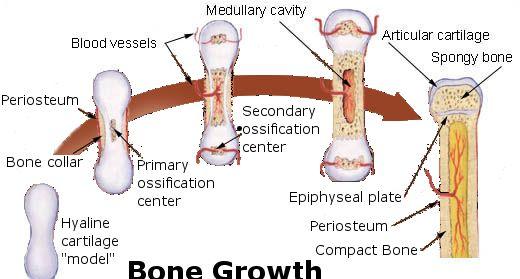

事实上,随着婴儿的长大,这些“散架”的软骨会慢慢的融合在一起,骨头之间的“缝隙”也会慢慢弥合。

在这个过程中,好几块骨头变成了一块骨头,所以等到婴儿长大成人,他的骨头数量就变少了。

而且在融合的同时,软骨也在慢慢变硬变成骨头,这个过程又叫做软骨内骨化,是包括人在内的哺乳动物胎儿产生骨组织的一个重要过程。

也就是说,婴儿比成人多出来的骨头最后融合在一起了。